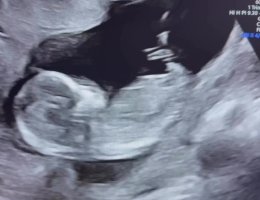

Her mener earlyglimpse at det er 95% gutt ut fra et bilde de har fått ut av en video.

Mens jordmor på tul og gyn på oul ikke helt klarer å se kjønn, men de tror jente. Begge sier de ikke klarer å se noe tegn til at det skal være gutt… men jeg er så nysgjerrig og klarer ikke tro på at det skal være jente når jeg har et så tydelig «gutte-nub» bilde..

i alle fall nå når de heller ikke så noe på oul..